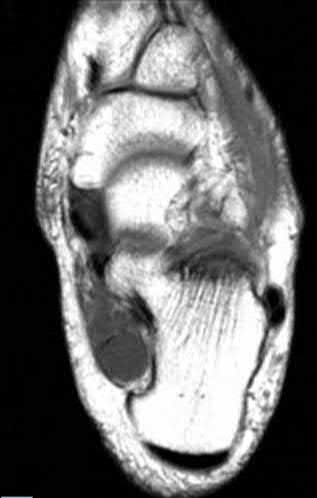

A 25-year-old male sustains an ankle fracture dislocation and undergoes open reduction and internal fixation. He returns to clinic five months following surgery complaining of continued ankle pain and instability with weight bearing. His immediate post-operative AP radiograph is seen in Figure A. Which of the following could have prevented this patient from developing persistent pain?

The patient presents with continued ankle pain and instability following open reduction and internal fixation. The radiograph in figure A demonstrates inadequate restoration of fibular length, likely leading to continued tibiotalar instability.